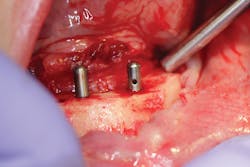

- All-on-4 (AO4) or a full-arch hybrid prosthesis that is fixed (figures 4 and 5).